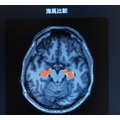

今回開発した技術は、将来の脳の委縮や記憶力に関連するといわれている「海馬」の体積の変化を可視化するもので、可視化された将来の脳の状態を見ることで加齢に伴う脳の変化を見ることができる。

記憶司令塔とも呼ばれている「海馬」に注目すると、海馬が萎縮しているのが解る。萎縮すると「認知機能」に影響が出る可能性が高いと言われているという。ただ、加齢に伴うシミュレーションのため、萎縮を抑える方法を生活に進んでとりいれることで、今後の萎縮を抑えられる機能性もある。例えば有酸素運動を適度におこなうことは海馬の萎縮を抑え、喫煙は海馬の萎縮を進行させてしまう調査結果もあるという。

この課題に対し、YUADの医学博士・精神科医・認知症専門医千葉悠平医師による医学的監修と、Biomyによる協力のもと、脳画像に画像生成技術の一つであるGAN(敵対的生成ネットワーク:本物に似たデータを生成する生成器と、本物のデータかどうかを見分ける判別モデルが、競い合いながら学習することで、高品質なデータを生成する技術)を活用することで、MRIで撮影した脳画像から将来の脳画像を予測する生成AIを開発。脳全体や認知症、記憶力と関連するといわれている海馬の体積が将来どのように変化するかを予測し、画像を生成する。